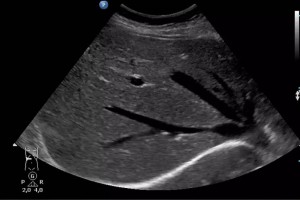

Diplomados en Ultrasonografía